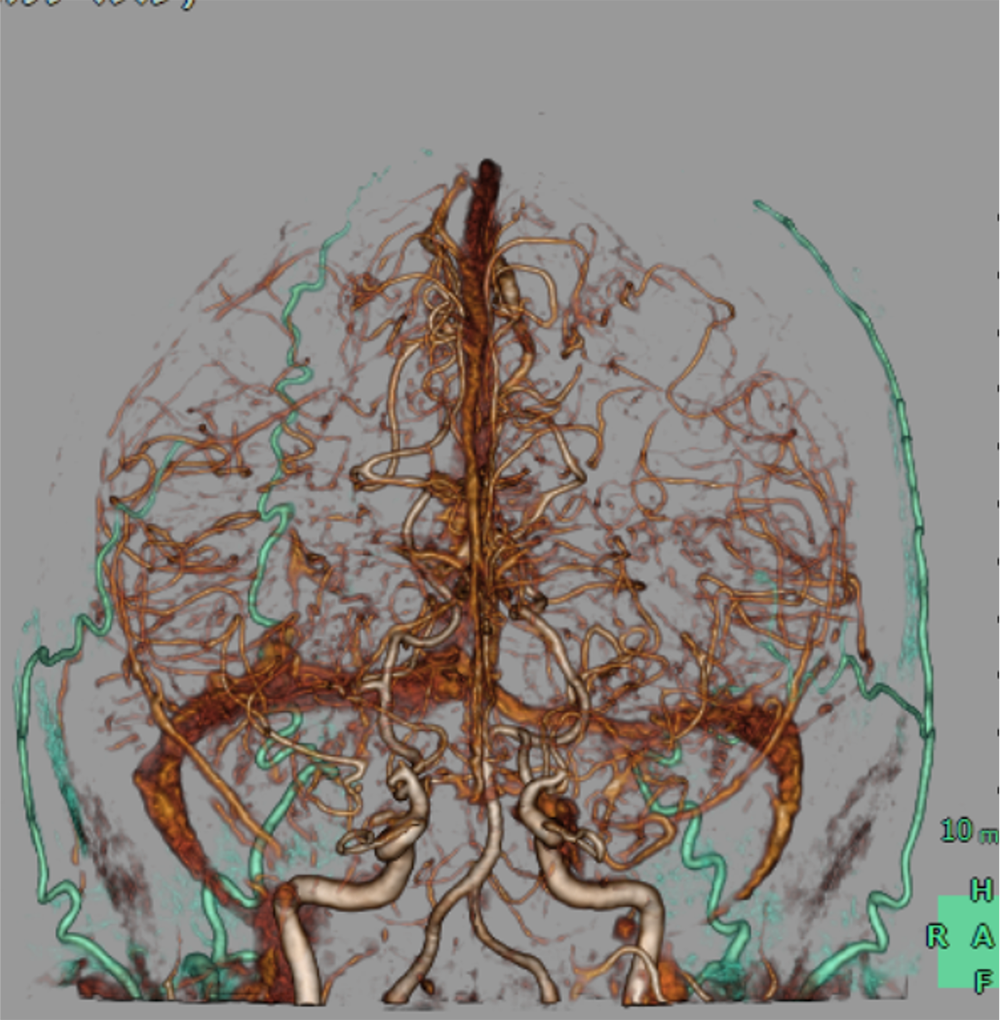

14歳ごろから手足の痺れやめまいなどを自覚しており、兄弟のもやもや病による脳卒中を契機にMRI撮像され、もやもや病と診断された。CTAで両側内頸動脈は閉塞しており、周囲に微細な増生血管をみとめた。前大脳動脈や中大脳動脈は狭窄しており、両側後大脳動脈に拡張を認めた。脳血流SPECTで左前頭葉、側頭葉に血流低下を認め、間接的血行再建術が施行された。

もやもや病における新生血管(もやもや血管)は血管径が細く、通常の撮影では明瞭な描出が難しいことがある。100kVの低管電圧撮影を用いることでもやもや血管の微細なネットワークを鮮明に描出し、病状評価や治療計画立案に役立てている。

血行再建術では、STA-MCAを直接吻合する方法のほか、STA、DTA、MMAなどを脳表と接続する間接血行再建術も広く施行されており、末梢の微細な血管解剖の取得までもが必要となる。

CT技術や撮像プロトコル設定について